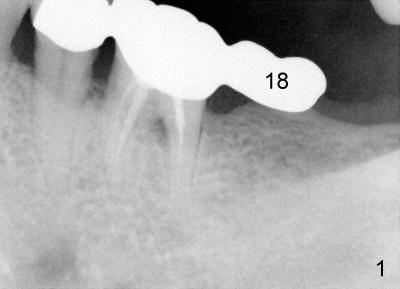

Fifty-four year old lady had had discomfort with a cantilever bridge (FPD) that restored #18 (Fig.1) and agreed to have FPD removed (Fig.2) and place implant (Fig.3: 5x8) 22 months ago. The lingual plateau of the implant was exposed due to plate perforation (Fig.4: <). At implant placement, #19 was found to have recurrent apical periodontitis. This tooth had root canal retreatment (Fig.5: 19), build-up (Fig.6: B) and crown (Fig.7: C).